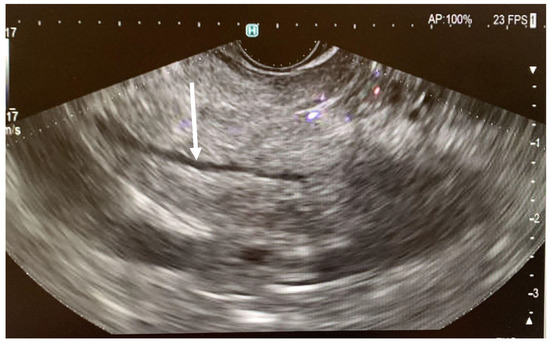

- Three endosonographic criteria have been suggested for the diagnosis of pancreas divisum with endoscopic ultrasound: (a) Inability to follow the main pancreatic duct from the major ampulla to the pancreas body; (b) Inability to follow the main PD from the hypoechoic ventral pancreas to the hyperechoic dorsal pancreas [40]; (c) The presence of the Stack sign as a possibility of pancreas divisum. The Stack sign is visualized better by positioning the radial echoendoscope (or by linear echoendoscope, reverse Stack sign) in the long scope position with the transducer in the duodenal bulb. When the balloon is inflated and advanced snugly into the apex of the bulb, the bile duct (closest to the transducer) and the pancreatic duct can be seen running in parallel through the pancreatic head [26,41]. Performing EUS, the Stack sign refers to the parallel alignment of three tubular structures seen in the region of the pancreatic head: common bile duct (CBD), ventral pancreatic duct (Wirsung’s duct), and dorsal pancreatic duct (Santorini’s duct). In pancreas divisum (positive Stack sign): the ventral and dorsal pancreatic ducts remain separate and on EUS, three parallel, stacked tubular structures are evident: (a) the CBD (most anterior); (b) the ventral pancreatic duct (Wirsung); (c) the dorsal pancreatic duct (Santorini) (most posterior). This triple-duct alignment is indicative of non-fusion and suggests pancreas divisum.

4. Case Presentation